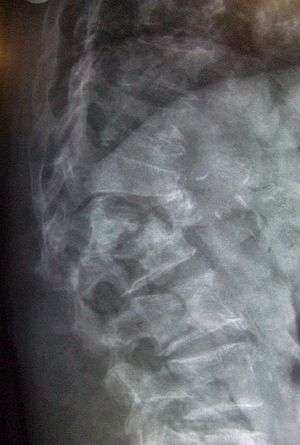

Multiple osteoporotic wedge fractures demonstrated on a lateral thoraco-lumbar spine X-ray

The diagnosis of osteoporosis can be made using conventional radiography and by measuring the bone mineral density (BMD).[76] The most popular method of measuring BMD is dual-energy X-ray absorptiometry. In addition to the detection of abnormal BMD, the diagnosis of osteoporosis requires investigations into potentially modifiable underlying causes; this may be done with blood tests. Depending on the likelihood of an underlying problem, investigations for cancer with metastasis to the bone, multiple myeloma, Cushing's disease and other above-mentioned causes may be performed.

Conventional radiography

Conventional radiography is useful, both by itself and in conjunction with CT or MRI, for detecting complications of osteopenia (reduced bone mass; pre-osteoporosis), such as fractures; for differential diagnosis of osteopenia; or for follow-up examinations in specific clinical settings, such as soft tissue calcifications, secondary hyperparathyroidism, or osteomalacia in renal osteodystrophy. However, radiography is relatively insensitive to detection of early disease and requires a substantial amount of bone loss (about 30%) to be apparent on X-ray images.

The main radiographic features of generalized osteoporosis are cortical thinning and increased radiolucency. Frequent complications of osteoporosis are vertebral fractures for which spinal radiography can help considerably in diagnosis and follow-up. Vertebral height measurements can objectively be made using plain-film X-rays by using several methods such as height loss together with area reduction, particularly when looking at vertical deformity in T4-L4, or by determining a spinal fracture index that takes into account the number of vertebrae involved. Involvement of multiple vertebral bodies leads to kyphosis of the thoracic spine, leading to what is known as dowager's hump.